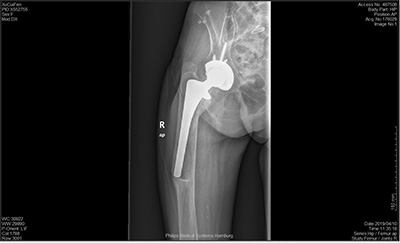

1、老年股骨頸骨折髖關(guān)節(jié)置換

對(duì)于老年股骨頸骨折或者部分粗隆間骨折,髖關(guān)節(jié)置換具有其獨(dú)特的優(yōu)勢(shì),科室將髖關(guān)節(jié)置換結(jié)合快速康復(fù)理念的應(yīng)用,在臨床上并取得了明顯的效果——有效的預(yù)防深靜脈血栓的形成,減少了臥床并發(fā)癥的發(fā)生,早期下地步行活動(dòng),明顯提高了老年術(shù)后患者的生活質(zhì)量。

2、髖關(guān)節(jié)翻修術(shù)

人工髖關(guān)節(jié)的平均壽命在15至20年左右,有于假體使用時(shí)間的延長(zhǎng),假體的磨損,將會(huì)出現(xiàn)關(guān)節(jié)松動(dòng)、下沉、磨損及假體周圍骨溶解等問(wèn)題,從而導(dǎo)致患者關(guān)節(jié)再次出現(xiàn)疼痛。如果人工關(guān)節(jié)松動(dòng)、脫位、髖臼磨損等問(wèn)題導(dǎo)致關(guān)節(jié)疼痛影響生活,可以通過(guò)人工髖關(guān)節(jié)翻修手術(shù)解決病人痛苦,提高生活質(zhì)量。